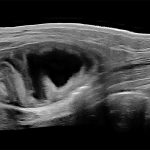

Imagini clinice:

Aplicatii: